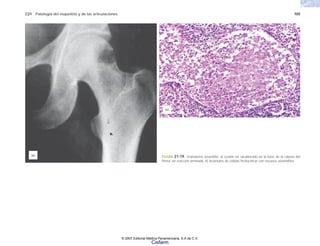

FIGURA 2-13. Histología de las vellosidades articulares en la artritis reumatoide. Hay proliferación de células sinoviales, infiltración inflamatoria y formación de pannus.

© 2007 Editorial Médica Panamericana, S.A de C.V.